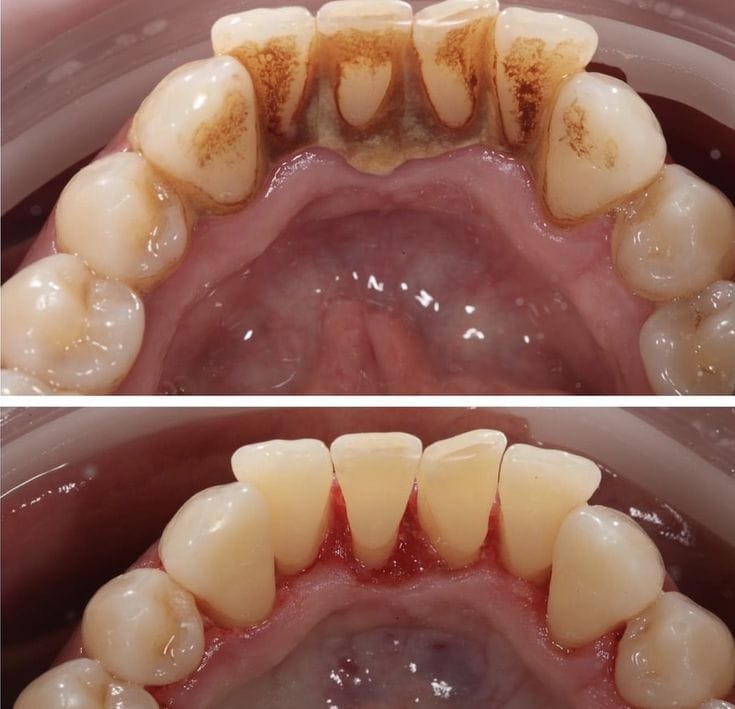

علاج أمراض اللثة

- تنظيف عميق للثة وجذور الأسنان (التقليح والتجريف).